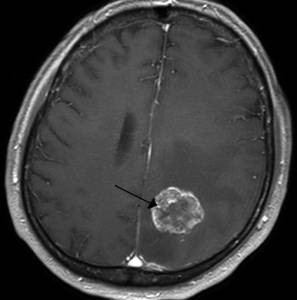

Злокачественная опухоль

Описание

Злокачественная опухоль представляет собой патологическое новообразование, состоящее из раковых клеток, которые быстро растут и могут метастазировать, что угрожает жизни человека.

Тип боли

Интенсивность и характер боли зависят от локализации опухоли, стадии заболевания и индивидуальных особенностей пациента.

Другие проявления

На ранних стадиях опухоль может не проявляться, пока не начнет активно расти. В этот момент состояние пациента ухудшается, могут возникать тошнота, утомляемость, рвота, нарушения слуха и зрения, трудности в распознавании речи, а также расстройства общей и мелкой моторики.

Клиническая картина рака разнообразна и сложна.

Методы диагностики и терапии

Диагностика включает КТ, МРТ, рентген, лабораторные анализы, гистологию и цитологию. Лечение обычно хирургическое, с возможным назначением курса химиотерапии или лучевой терапии, а затем длительного поддерживающего медикаментозного лечения.